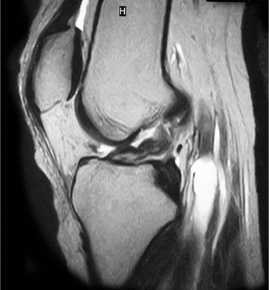

• ACL 손상 방사선 사진3